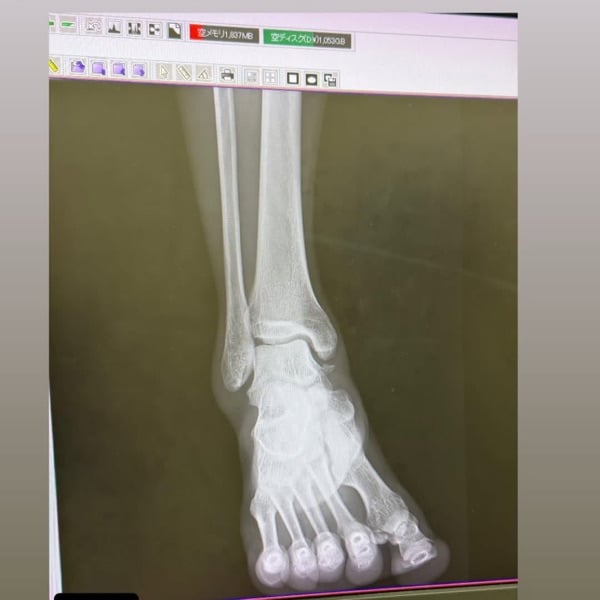

一つ前までのゲストに来てくださったペヤングくんから、ショッキングな画像が届いた! 足首が痛くてレントゲンとエコーを撮った結果! 靭帯全損症、骨が取れている、軟骨損傷…どうも重症みたい。 まあこんなにハードなスポーツをやっているので、大小あれど故障は付きもの。全く走れない時期や、思い通りのトレーニングが積めない日々…心が折れそうでも、それを乗り越えてたくさんの偉大な先輩方が復活しています。 ま、人生の一部とはいえ、ただの趣味!気長に前向きに付き合って行きましょう!というアホみたいな話をしました笑!よかったら聴いてください〜✨ #トレイルランニング #トレラン #靭帯損傷 #軟骨損傷